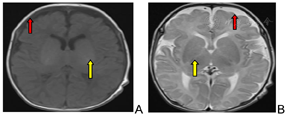

实验室及相关辅助检查:血生化、甲状腺激素功能三项、血氨、乳酸、铜蓝蛋白、同型半胱氨酸:均正常;血、尿氨基酸遗传代谢筛查:未见异常。心脏超声:先天性心脏病;房间隔缺损(小);卵圆孔未闭;降主动脉与肺动脉间异常血流束(侧枝?)。头颅磁共振(MRI)提示:双侧额颞部蛛网膜下腔增宽,髓鞘化落后正常同龄儿(图1)。长程视频脑电图(VEEG)提示:发作间期可见广泛性多灶棘波、棘慢波发放,伴随有爆发-抑制现象图形(图2)。

研究表明,GNAO1基因变异导致DDE的头颅MRI常无特异性改变,早期表现为蛛网膜下腔增宽、髓鞘形成延迟,部分可出现弥漫性的脑萎缩、先天性胼胝体结构变薄[19,21]。本例患者头颅MRI表现均为不同程度额颞部蛛网膜下腔稍增宽,髓鞘化落后于正常同龄儿,与上述相关报道相一致。